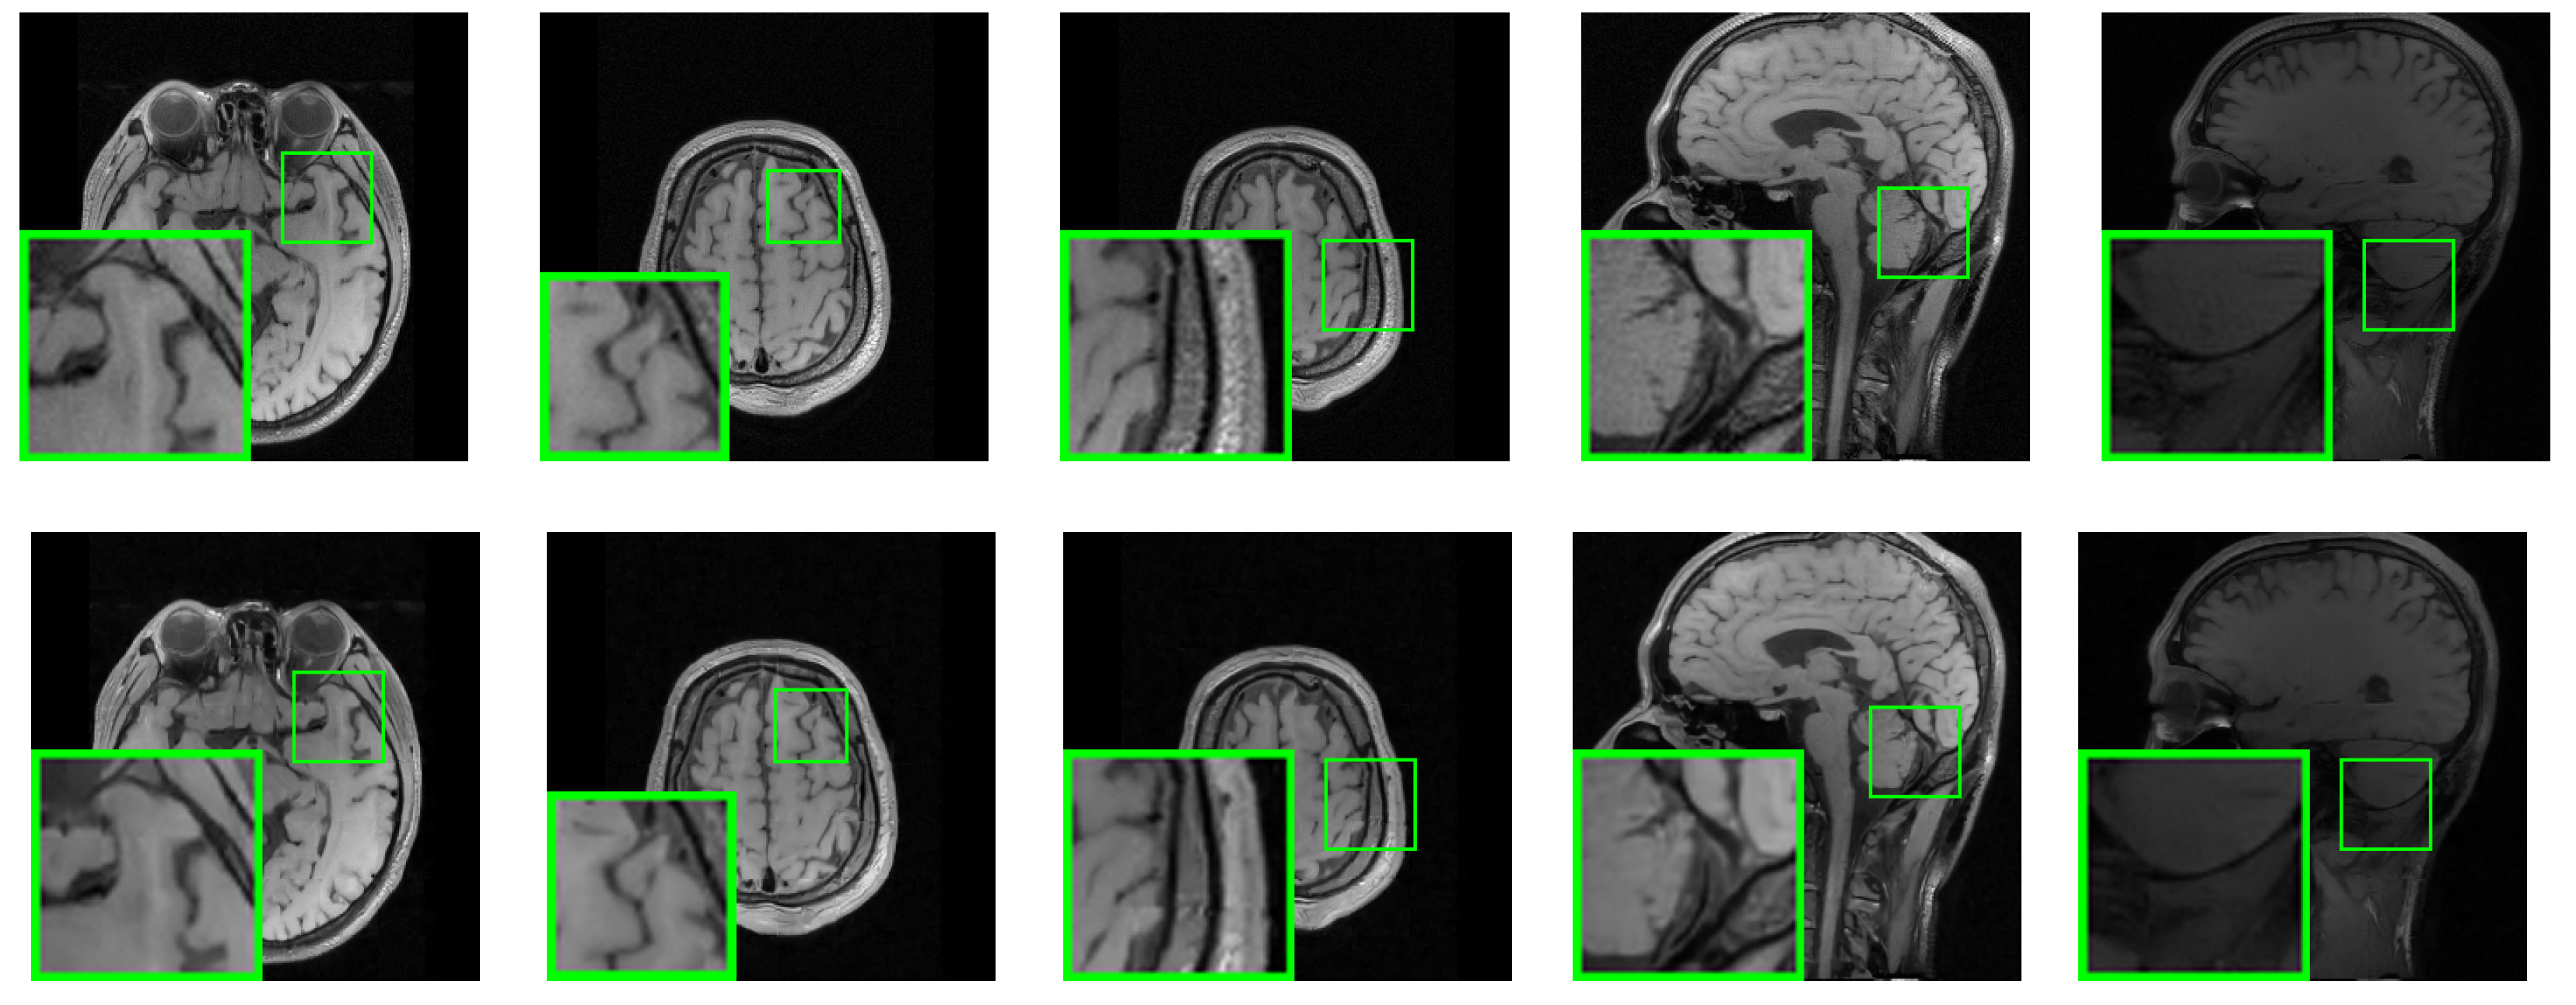

3.2. Analysis of Experimental Results